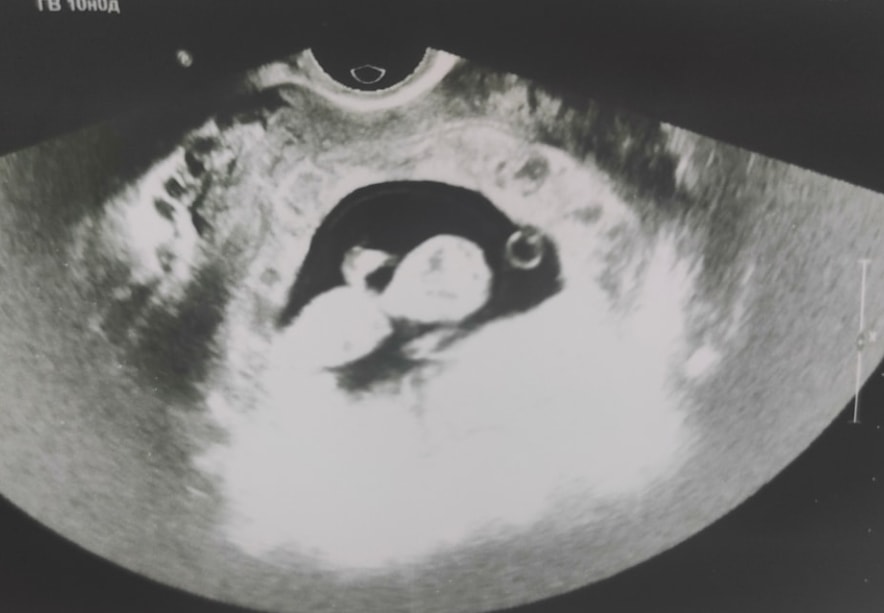

Вот 10 недельИзображение